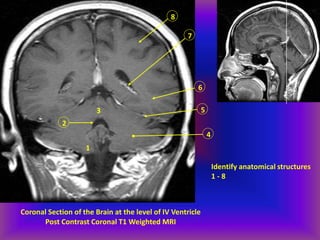

Coronal Section of the Brain at the level of IV Ventricle

Post Contrast Coronal T1 Weighted MRI

Identify anatomical structures

1 - 8

1. Cerebellar tonsil

2. Cerebellar hemisphere

3. IV ventricle

4. Superior vermis

5. Tentorium

6. Posterior temporal lobe

7. Choroid plexus within lateral

ventricle

8. Posterior frontal lobe